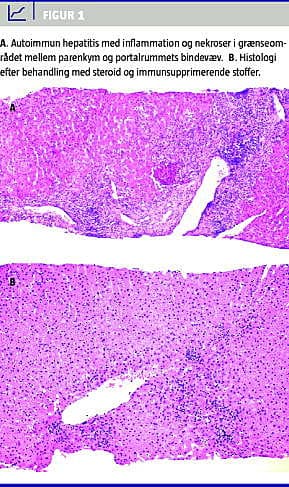

Det anbefales at tage en leverbiopsi ved mistanke om AIH. Histologisk findes interfasehepatitis, dvs. inflammation og nekroser i grænseområdet mellem parenkymet og portalrummenes bindevæv (piecemeal -nekroser) samt plasmacelleinfiltration (Figur 1 ) [20]. Der er ikke forskel på sværhedsgraden af histologisk sygdom hos hhv. symptomatiske og asymptomatiske patienter, fraset manifest cirrose, som i nogle studier er påvist lidt hyppigere ved symptomgivende sygdom. Ved debut med akut leversvigt er histologien overvejende præget af akutte forandringer, således er der mere udtalt interfasehepatitis og nekroser, men mindre fibrose og cirrose [13].

Målet for behandling er at opnå tidlig, komplet og vedvarende remission af den inflammatoriske proces i levervævet (Figur 1) med anvendelse af lavest mulige medicindoser. Ved remission forstås opnåelse af symptomfrihed samt normalisering af biokemi og histologi.